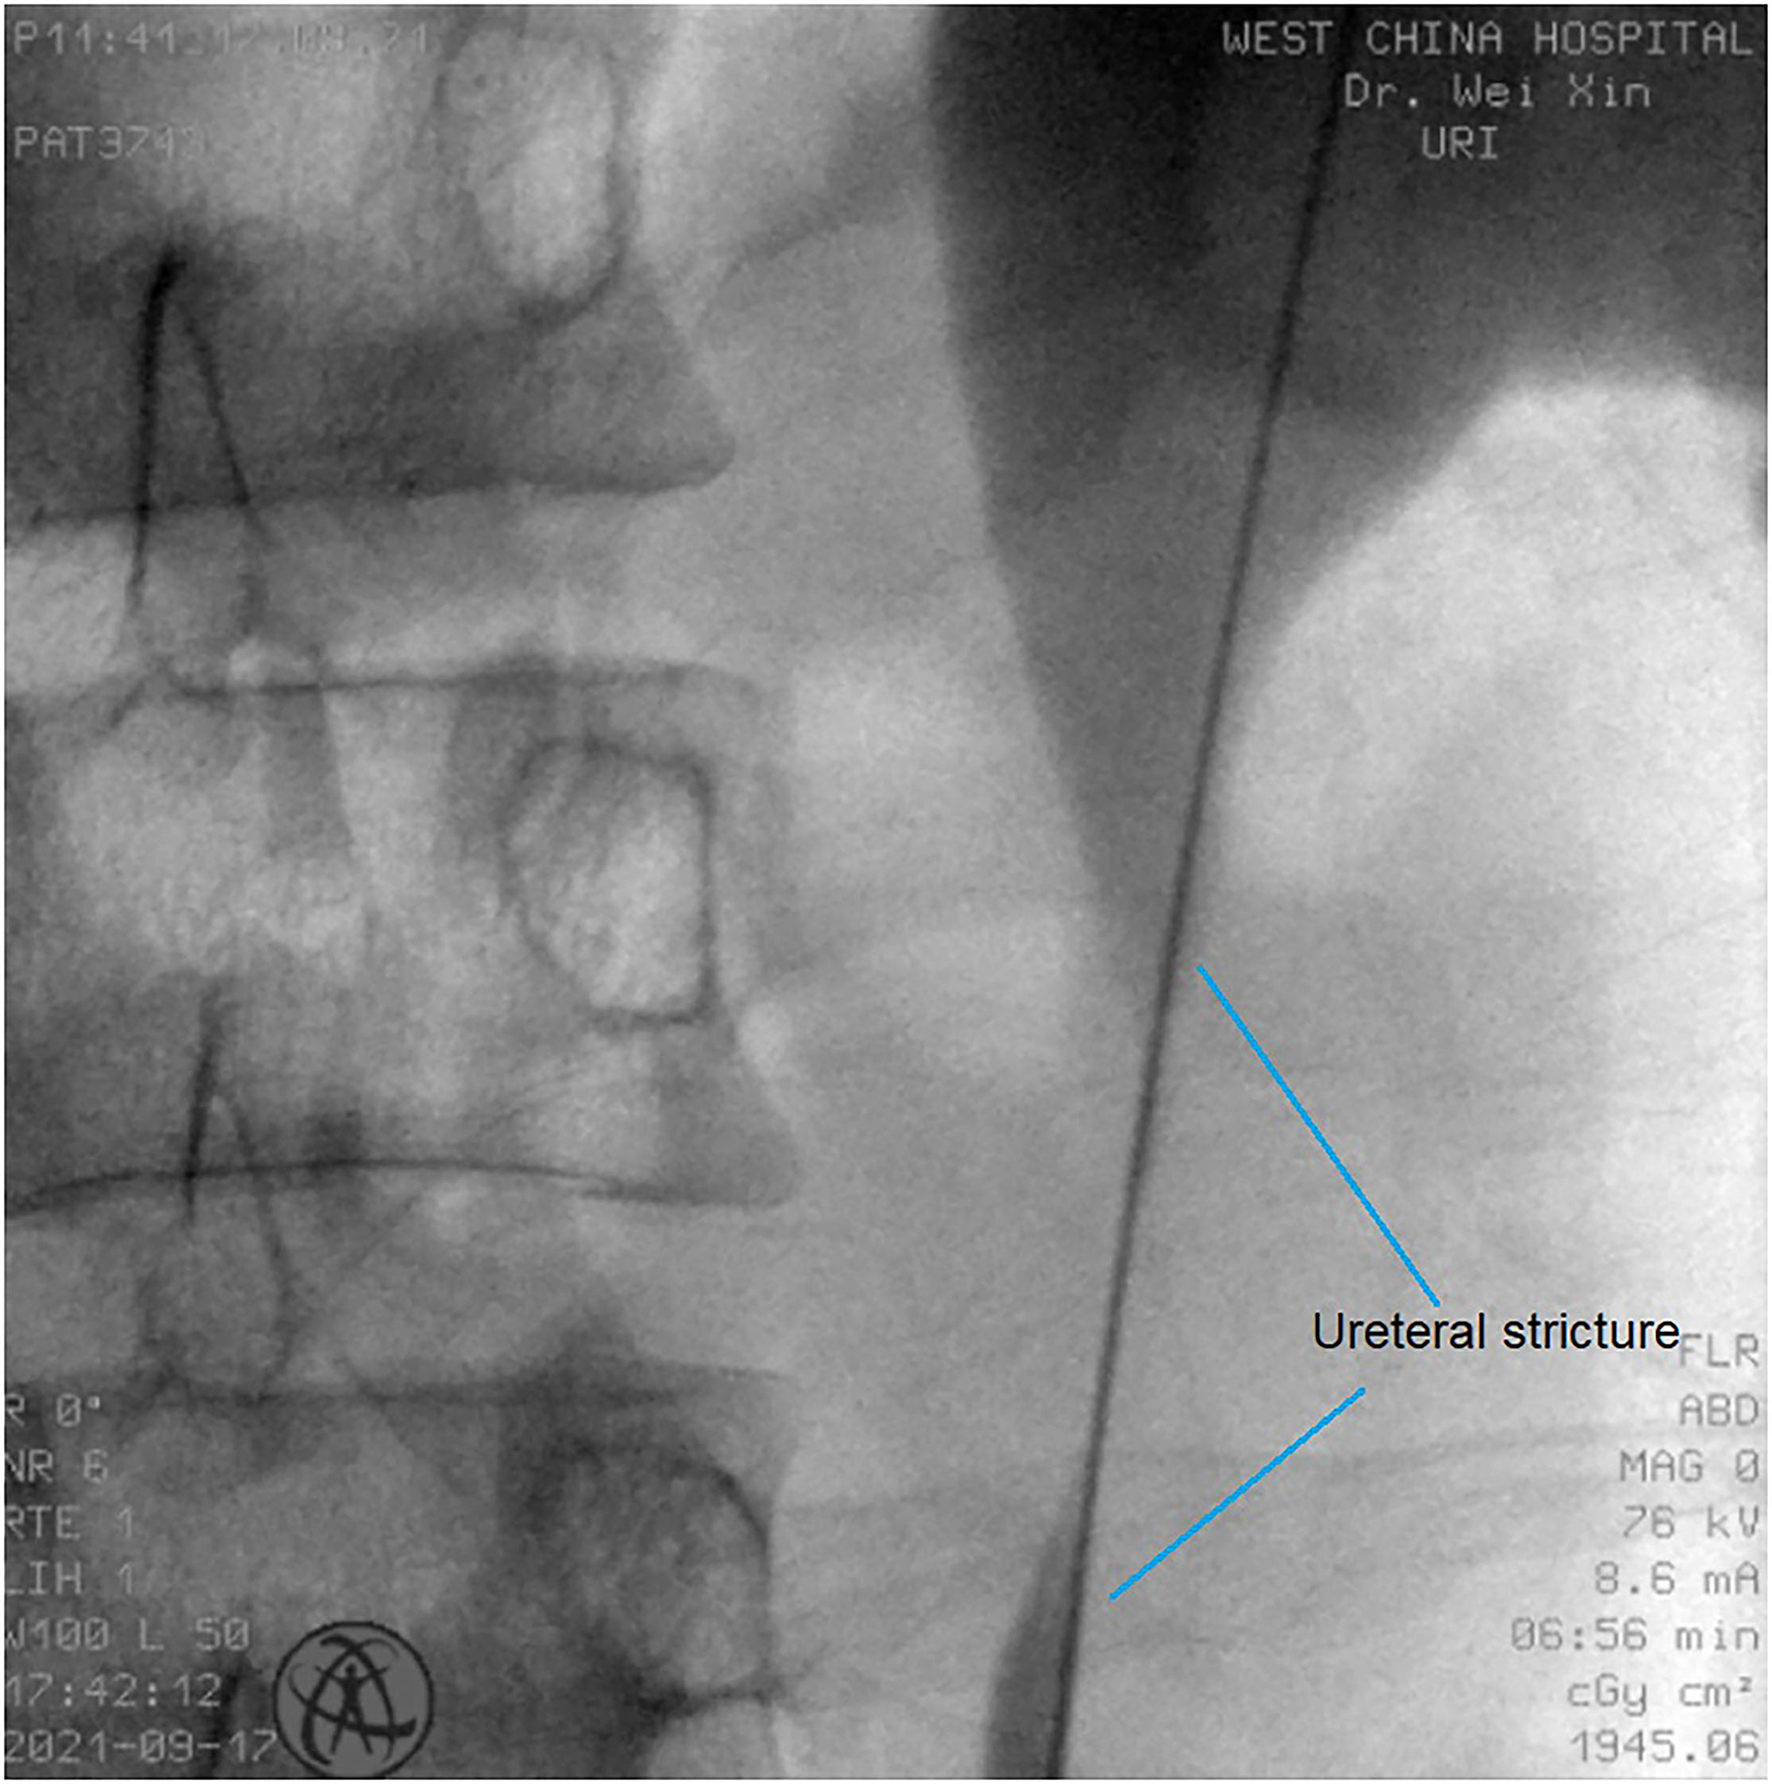

All operations were performed by the same endourological skilled surgeon. The surgical procedures were similarly to our previously reported (10, 11). The position and length of ureteral stricture are determined by retrograde or antegrade ureterogram (Figure 1). The two Allium Stents, 10 and 12 cm, are currently available in our hospital. Different stents were selected according to the length of the ureteral strictures. All ureteral strictures were diluted by 18 F or 21 F balloon before the MUS was retrogradely implanted. After confirming that the narrowed segment was dilated satisfactorily, a 24 F or 30 F-coated metal ureteral stent was inserted. We initially implanted one stent for proximal ureteric stricture, and found that the stents migration rate was as high as 80% (Figure 2). So, we improved the surgical technique and inserted two stents in tandem for proximal ureteral strictures and long strictures (Figure 3). When the stent was released satisfactorily, radiography was performed again to confirm the stent position and patency. The migration stents were endoscopically adjusted to the normal position or exchanged as we previous reported (11).

Figure 1

The position and length of ureteral stricture are determined by retrograde or antegrade ureterogram.